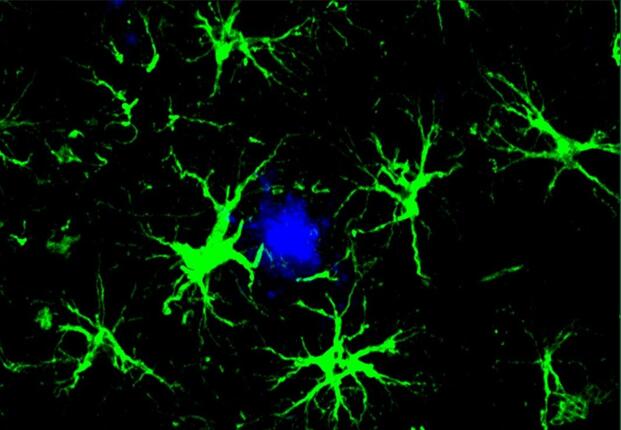

Researchers removed T cells from healthy mice, modified them to target amyloid beta, and injected them into six-month-old mice that had been genetically engineered to develop Alzheimer’s-like amyloid plaques. The mice received three injections spaced 10 days apart. Ten days after the final injection, the treated mice showed significantly greater reduction in amyloid plaques compared to mice that received unmodified T cells. The brains of treated mice also showed reduced activation of microglia and astrocytes, two cell types associated with the neuroinflammation that accompanies Alzheimer’s.